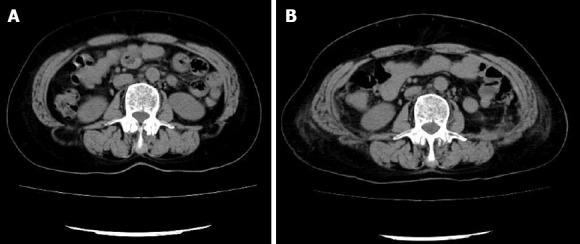

A lumbar hernia is a rare entity, and a bilateral lumbar hernia is much rarer. From May 2015 to October 2017, we treated only three patients with bilateral lumbar hernias. One patient came to the hospital presenting with right-sided abdominal pain, and the other two patients presented with bilateral lumbar masses. The previous bilateral lumbar hernia reported in the literature was repaired by open surgery. The laparoscopic approach the transabdominal preperitoneal (TAPP) procedure with the self-gripping Parietex ProGrip™ mesh was performed at our center. The laparoscopic repair was conducted by a skilled hernia surgeon, and was successfully performed in the three patients. The patients resumed a semi-liquid diet and had no activity restriction after six hours following the operation. No antibiotics were used after the surgery. The operative times of the three patients were 120 min, 85 min, and 130 min. The blood loss volumes of the three patients were 20 mL, 5 mL, and 5 mL. The visual analogue scale pain scores of the three patients were 1, 2, and 2 on postoperative day 1, and were 1, 2, and 1 on postoperative day 3. No perioperative complications, such as bulge, wound infection and hematoma, occurred after the surgery. All of the patients were discharged on the third day after the operation. There was no chronic pain and no hernia recurrence during the follow-up. This study showed that the laparoscopic TAPP approach with the self-gripping mesh is safe and feasible, and can be considered an alternative method for the treatment of bilateral lumbar hernias.

腰椎疝是一种罕见的病症,双侧腰椎疝则更为罕见。2015年5月至2017年10月,我们仅治疗了3例双侧腰椎疝患者。1例患者因右侧腹痛入院,另外2例患者表现为双侧腰部肿块。文献中报道的既往双侧腰椎疝均通过开放手术修复。我们中心采用腹腔镜经腹腹膜前(TAPP)手术并使用自固定的百达思ProGrip™补片。腹腔镜修复手术由一位经验丰富的疝外科医生进行,3例患者均手术成功。术后6小时患者即可恢复半流质饮食且无活动限制。术后未使用抗生素。3例患者的手术时间分别为120分钟、85分钟和130分钟。3例患者的失血量分别为20毫升、5毫升和5毫升。3例患者术后第1天的视觉模拟评分疼痛分数分别为1分、2分和2分,术后第3天分别为1分、2分和1分。术后未发生围手术期并发症,如隆起、伤口感染和血肿。所有患者均在术后第3天出院。随访期间无慢性疼痛且无疝复发。本研究表明,使用自固定补片的腹腔镜TAPP手术方法安全可行,可被视为治疗双侧腰椎疝的一种替代方法。